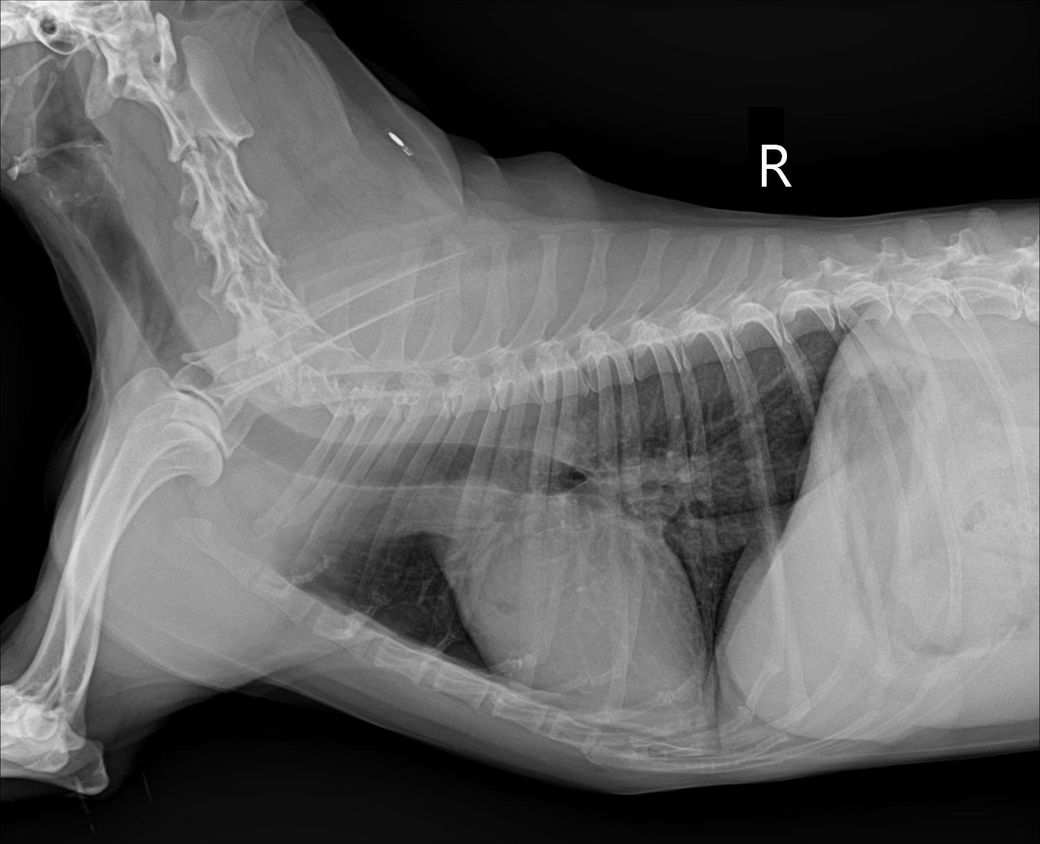

간크기 작다고 하는데 어디를봐야 작은걸 알수있을까요?? 정말 간이 작은 편인건도 궁금합니다!!

믹스(중성화o), 몸무게9.3kg 입니다